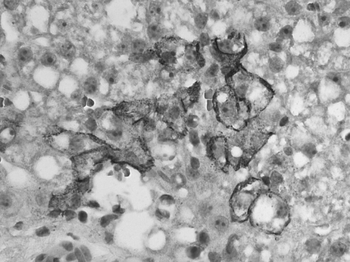

Randomly distributed single-cell necrosis is a histopathologic feature observed in lymphocytic choriomeningitis virus infection.